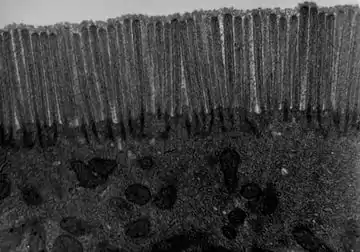

Transmission electron microscope (TEM) image of human jejunum

Structure

The interior surface of the jejunum—which is exposed to ingested food—is covered in finger–like projections of mucosa, called villi, which increase the surface area of tissue available to absorb nutrients from ingested foodstuffs. The epithelial cells which line these villi have microvilli. The transport of nutrients across epithelial cells through the jejunum and ileum includes the passive transport of sugar fructose and the active transport of amino acids, small peptides, vitamins, and most glucose. The villi in the jejunum are much longer than in the duodenum or ileum.

- The villi of the jejunum look like long, finger-like projections, and are a histologically identifiable structure.